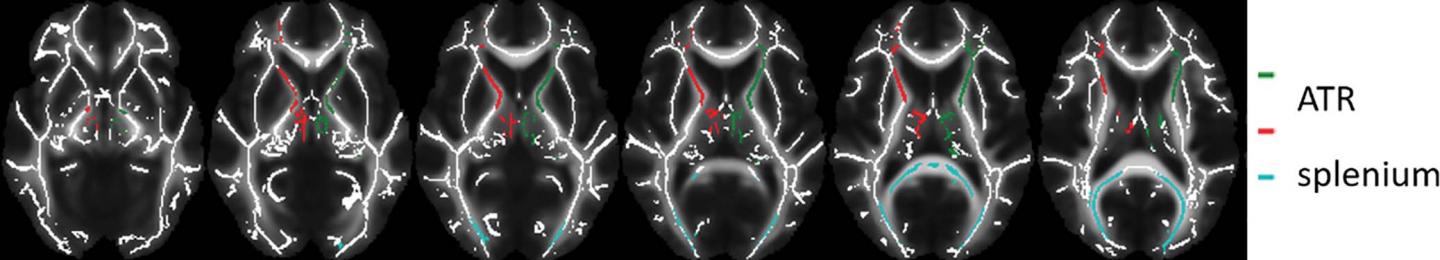

image: Images of regions of interest (colored lines) in the white matter skeleton representation. Data from left and right anterior thalamic radiation (ATR) were averaged.

Patients received either MPH or a placebo for 16 weeks. Before and one week after treatment cessation, the participants underwent MRI including diffusion tensor imaging (DTI), a technique that helps assess white matter. DTI provides a measure called fractional anisotropy (FA), which is thought to reflect important aspects of white matter such as nerve fiber density, size and myelination--the process of coating nerve fibers to protect the nerve and help it carry signals more efficiently.